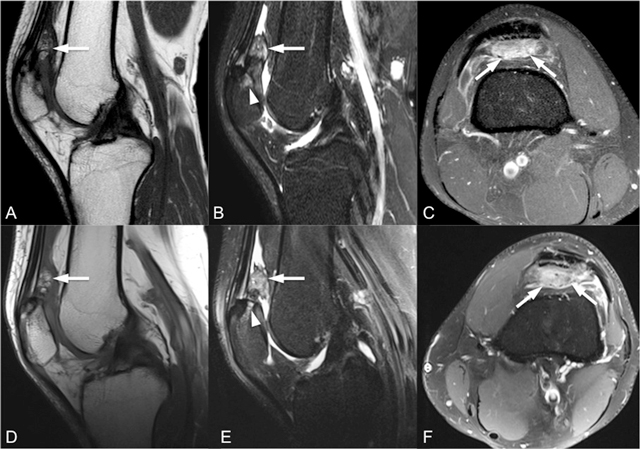

Figure 2

Sagittal T1-weighted (A, D), sagittal fat-saturated T2-weighted (B, E) and intravenous contrast-enhanced axial fat-saturated T1-weighted (C, F) MR images (top row for right knee, bottom row for left knee) show enlarged and inflamed quadriceps fat pad indicated by increased signal intensity with convex posterior border and contrast enhancement by intravenous contrast administration (arrows).